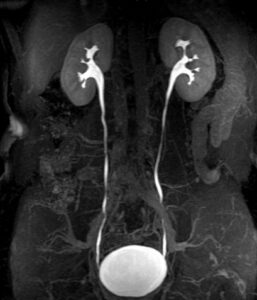

در تصویربرداری MRU یا ام آر آی سیستم ادراری، مشاهده کلیه ها، حالب و مثانه با استفاده از داروی ادرار آور و ماده حاجب مناسب بدن بیمار انجام می شود.

ام آر اوروگرافی MR Urography از روش های پیشرفته برای تصویربرداری از مسیر ادراری است. با استفاده از تصویربرداری MRU یا ام آر آی سیستم ادراری بررسی وسیع سیستم جمع آوری ادرار، پارانشیم کلیوی و ساختارهای اطراف فراهم می شود.

تصویربرداری مجاری ادراری (MRU) شامل مجموعه ای از روش های ارزیابی بهینه و غیر تهاجمی برای بسیاری از ابنورمالی ها (ناهنجاری) مسیر ادراری است. این روش برای تشخیص بالینی انسداد احتمالی مسیر ادراری، هماچوریا و ناهنجاری های مادرزادی سیستم ادراری و تغییر آناتومی در اثر جراحی، به ویژه در کودکان و بانوان باردار و کسانی که نباید در معرض پرتو های یونیزان قرار بگیرند کاربردی است.

هدف از انجام ام ار یو کلیه و سیستم ادراری بررسی عملکرد کلیه ها و چگونگی ترشح ادرار و همچنین وجود تومورها و انسدادهای ناشی از سنگ و انتشار آن ها به قسمت های مجاور است.